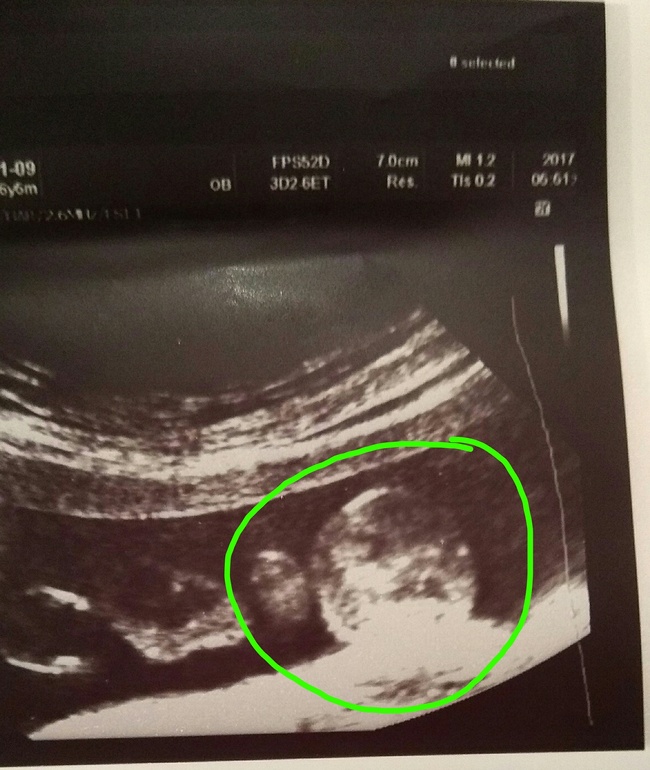

Всё у нас хорошенько, как опережали, так и продолжаем в том же духе. Головастик у нас растет и на попе спокойненько сидит, но после утренних попыток выбраться с меня через мой бок я не удивлена, что перевернулся на попу

Божечки, какой он сладкий присладки, перед узи я сьела мароженку, а он так причмокивал и язычок высовывал, наверное ему тоже понравилось

. Во время узи с врачом и поговорили, и посмеялись, дала пару фоток, делюсь с вами, ну и параметры на память